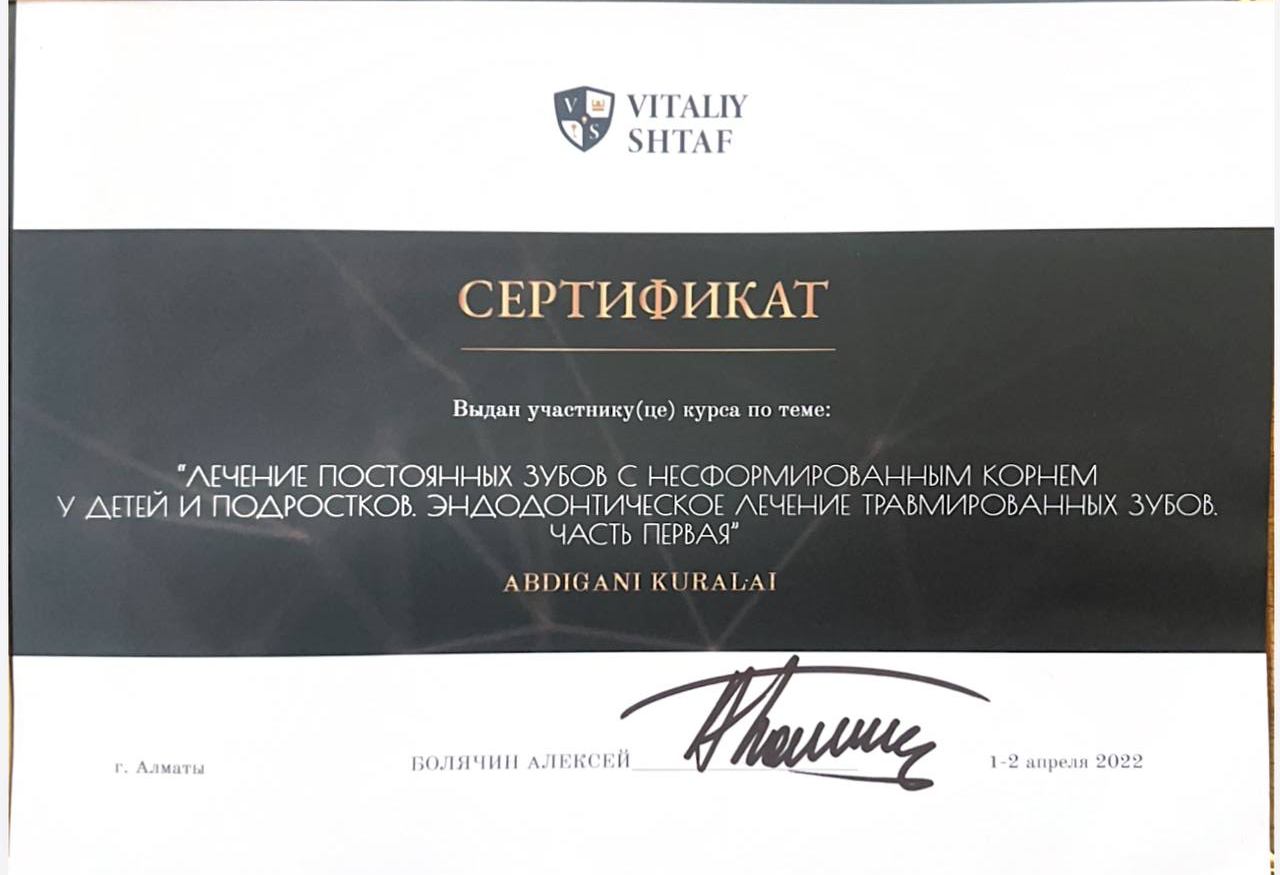

Абдигани Куралай Талгатовна

Регулярно повышает квалификацию, посещает семинары и мастер-классы